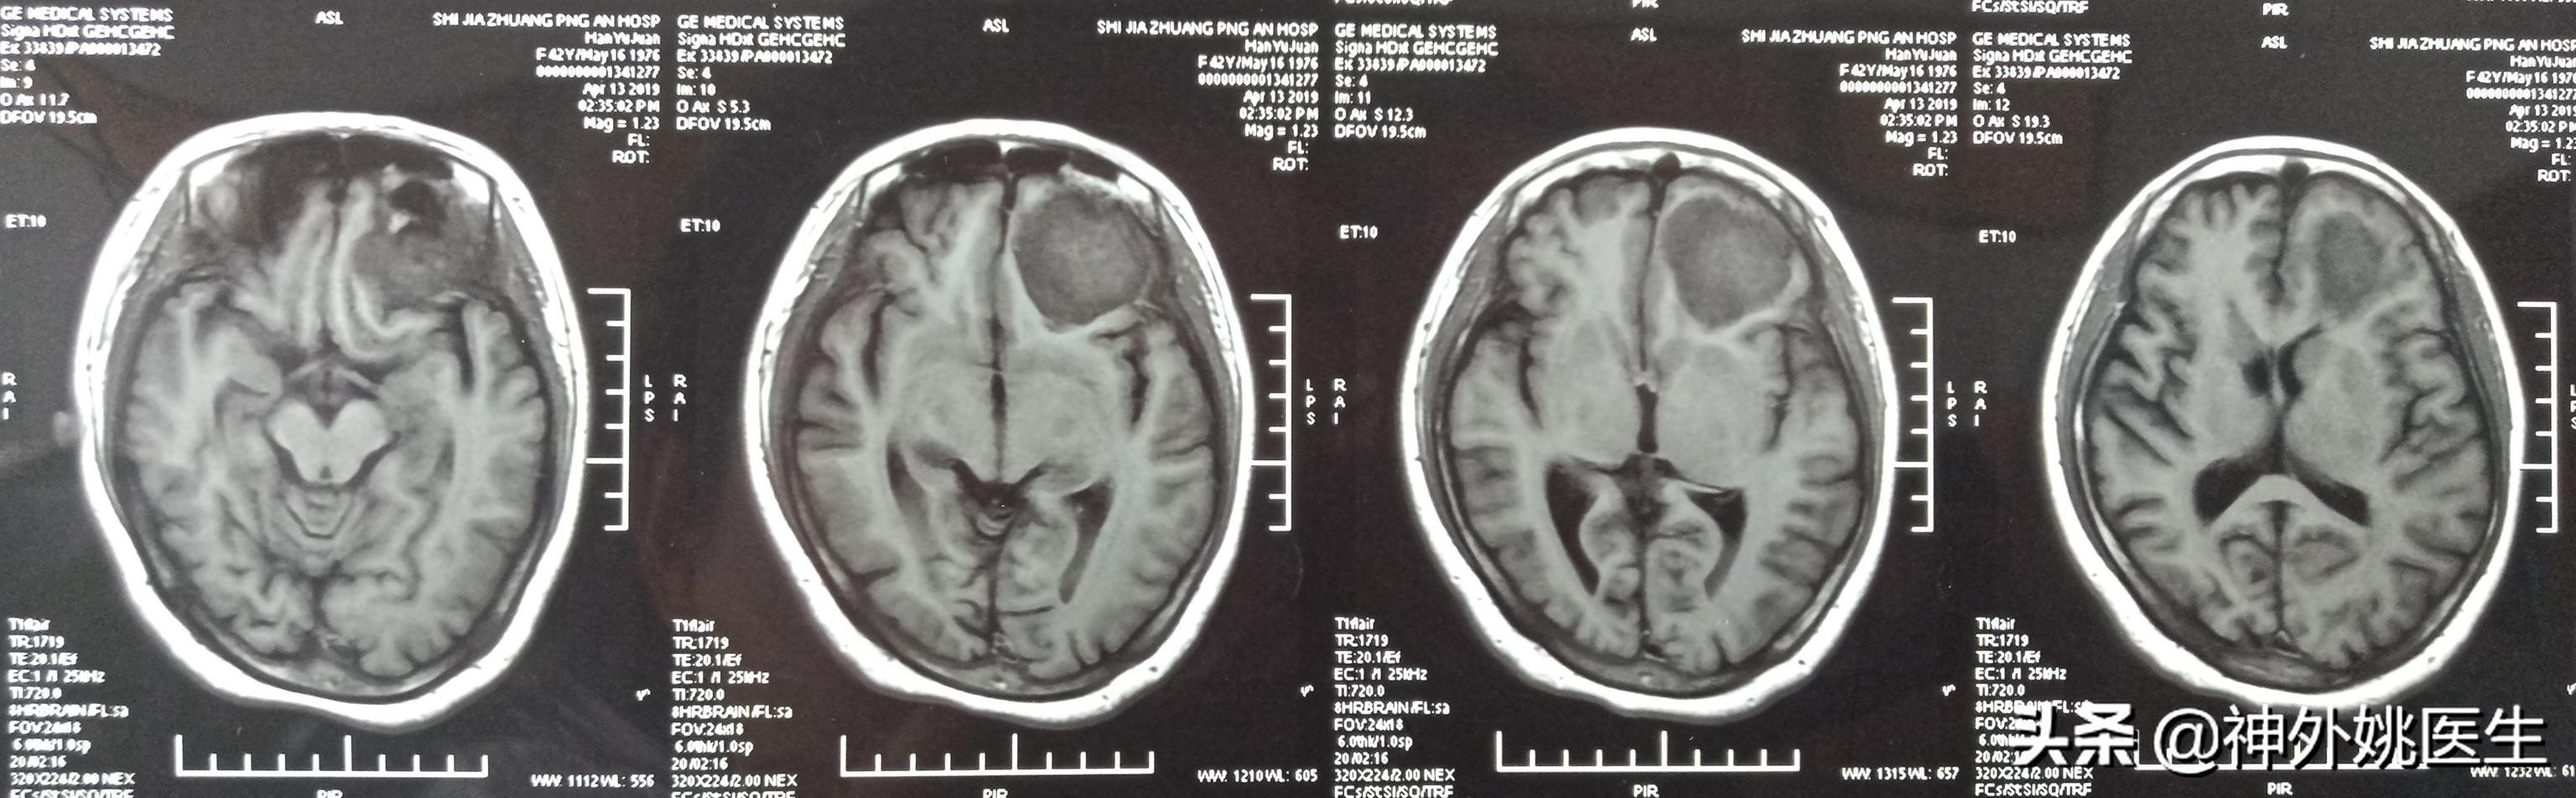

头MRI检查:1、左额部脑膜瘤。2、左侧放射冠区腔隙性脑梗死。(图3-7)

图3 T1像病变呈稍长T1信号。

图4 T1像病变呈稍长T2信号。

图7 病变基底位于颅底硬膜,可见脑膜尾征,病变大小约3.8cm x 4.1cm x 2.9cm。